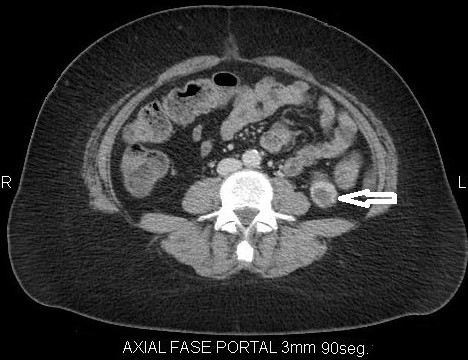

Fase excretora o arterial tardía

Comienza aproximadamente a los 3 minutos posteriores a la inyección del medio de contraste y permite evaluar su excreción por el sistema colector; por lo tanto, es útil para evaluar la relación de la masa con los cálices y la pelvis renal y llegar a una mejor planificación quirúrgica conservadora en un caso dado 3-4 (Fig. 4).